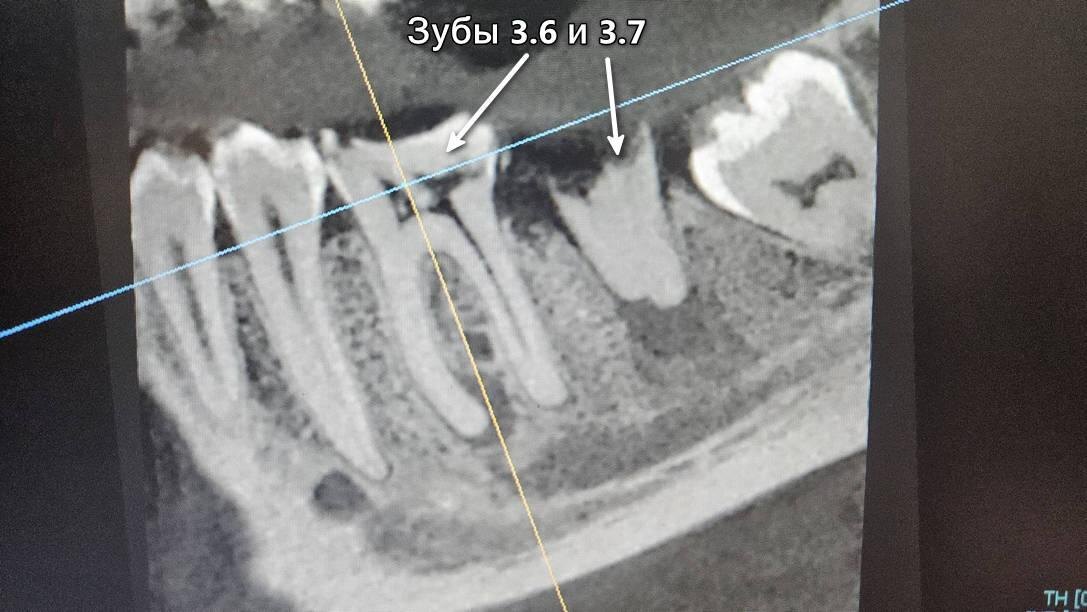

Зуб 3.7 давно разрушен, он не беспокоил Владимира, поэтому мужчина не спешил лечить его терапевтически или удалять. По результатам визуального осмотра, перкуссии и пальпации выяснили, что источниками боли являются два зуба: 3.6 и разрушенный 3.7. Для полного понимания ситуации в полости рта направили пациента на рентген📸

Источники острой боли: зубы 3.6 и 3.7